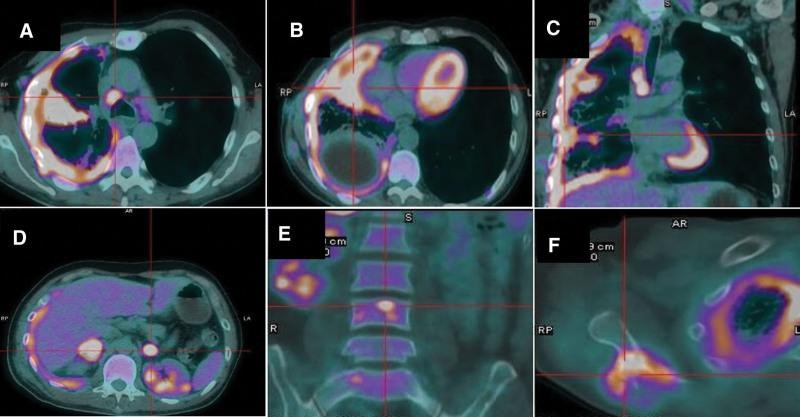

患者男性,54 岁,每年吸烟约 30包,咳嗽、胸痛 1 个月,2019 年 11 月入我院,胸部 CT 示有 2 cm 肿块,有空洞。右肺中叶,纵隔淋巴结肿大,右胸膜弥漫性胸膜增厚,右胸胸腔积液。随后的正电子发射断层扫描-计算机断层扫描 (PET-CT) 扫描证实了右肺肿块和厚胸膜中葡萄糖代谢异常增加(图 1A-C)。它还显示双侧肾上腺、右侧肩胛骨和多个椎骨的全身转移(图 1D-F)。实验室检查结果在正常范围内,除了碳水化合物抗原 125 水平升高, 为490.2 U/ml 。进行了胸腔穿刺术,但在反复剥脱细胞学检查后,引流的胸腔液中未发现肿瘤细胞。接下来,支气管镜检查显示右中支气管开口处有压缩性支气管狭窄,但病理结果显示没有恶性细胞。随后对肿块进行CT引导下细针穿刺活检,活检标本病理仅显示凝固性坏死和肺组织异常。最后,使用电视胸腔镜进行胸膜活检,活检标本呈恶性肿瘤细胞。免疫组化染色显示肿瘤TTF-1和Napsin A阴性,但P40和CK5/6阳性(图 2A-C)。因此,该患者被诊断为鳞状细胞肺癌(美国癌症联合委员会第 8 版 T3N2M1c,IVB 期)。通过 ARMS-PCR 程序检测 EGFR 外显子 19 缺失突变。使用抗体 22C3 (Dako pharmDx) 对 PD-L1 表达的评估显示 肿瘤阳性细胞数 为 90%(图2D)。

图1:PET-CT扫描。PET-CT显示右肺肿块糖代谢异常增加,纵隔淋巴结肿大,右侧胸膜弥漫性增厚。此外,还发现了双侧肾上腺、右侧肩胛骨和多处椎骨的全身转移。